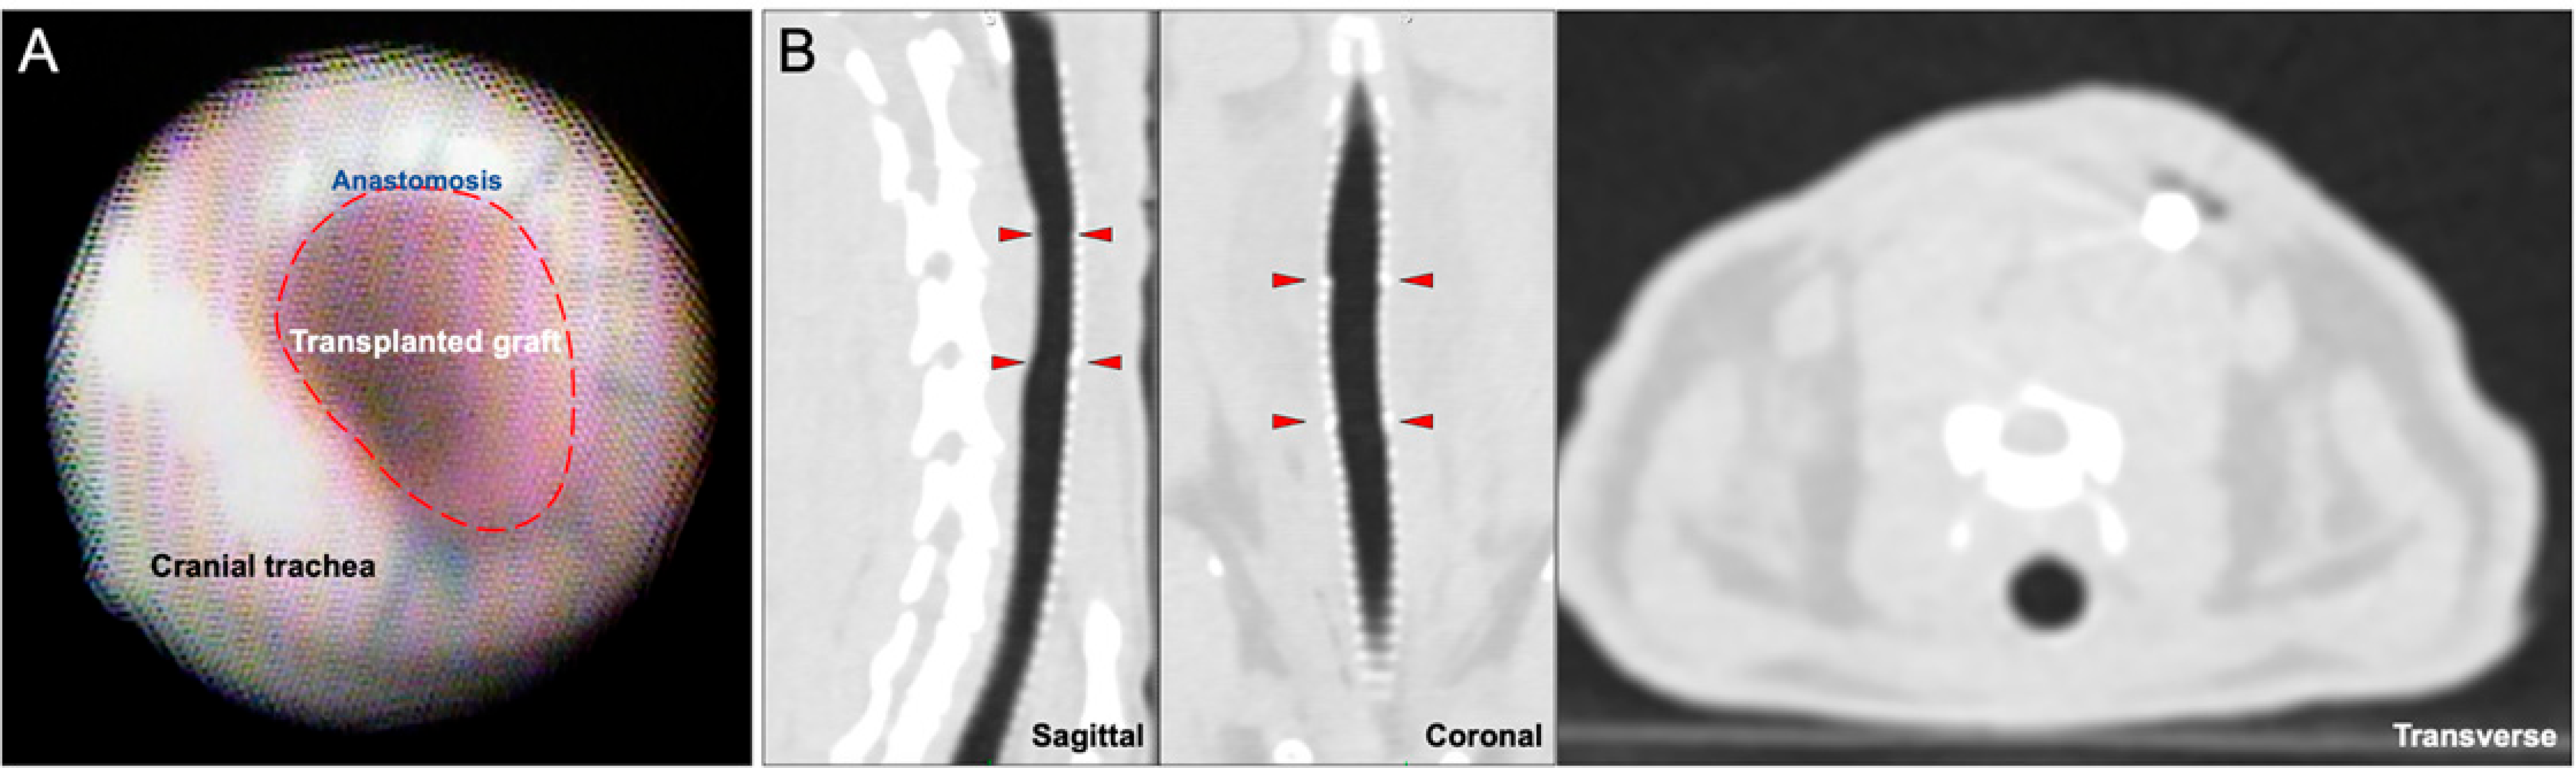

Bronchoscopic examination in all tracheas showed normal, pink mucosa without patches of ischemia or necrosis. There was scattered hyperemia that was not attributable to any one treatment group. No suture line dehiscence was observed, and the pediatric bronchoscope was able to traverse both the proximal and distal anastomoses without difficulty (Figure 2A). CT showed overall luminal patency without extra-tracheal air (Figure 2B).

Figure 2.

Bronchoscopic and Radiographic Surveillance at 7 Days Post-transplant. (A) Bronchoscopy shows a patent tracheal graft without evidence of necrosis. (B) Sagittal, coronal, and transverse views show intact tracheal anastomosis without stenosis or extraluminal air suggestive of dehiscence. The red arrowheads indicate the proximal and distal anastomotic boundaries.